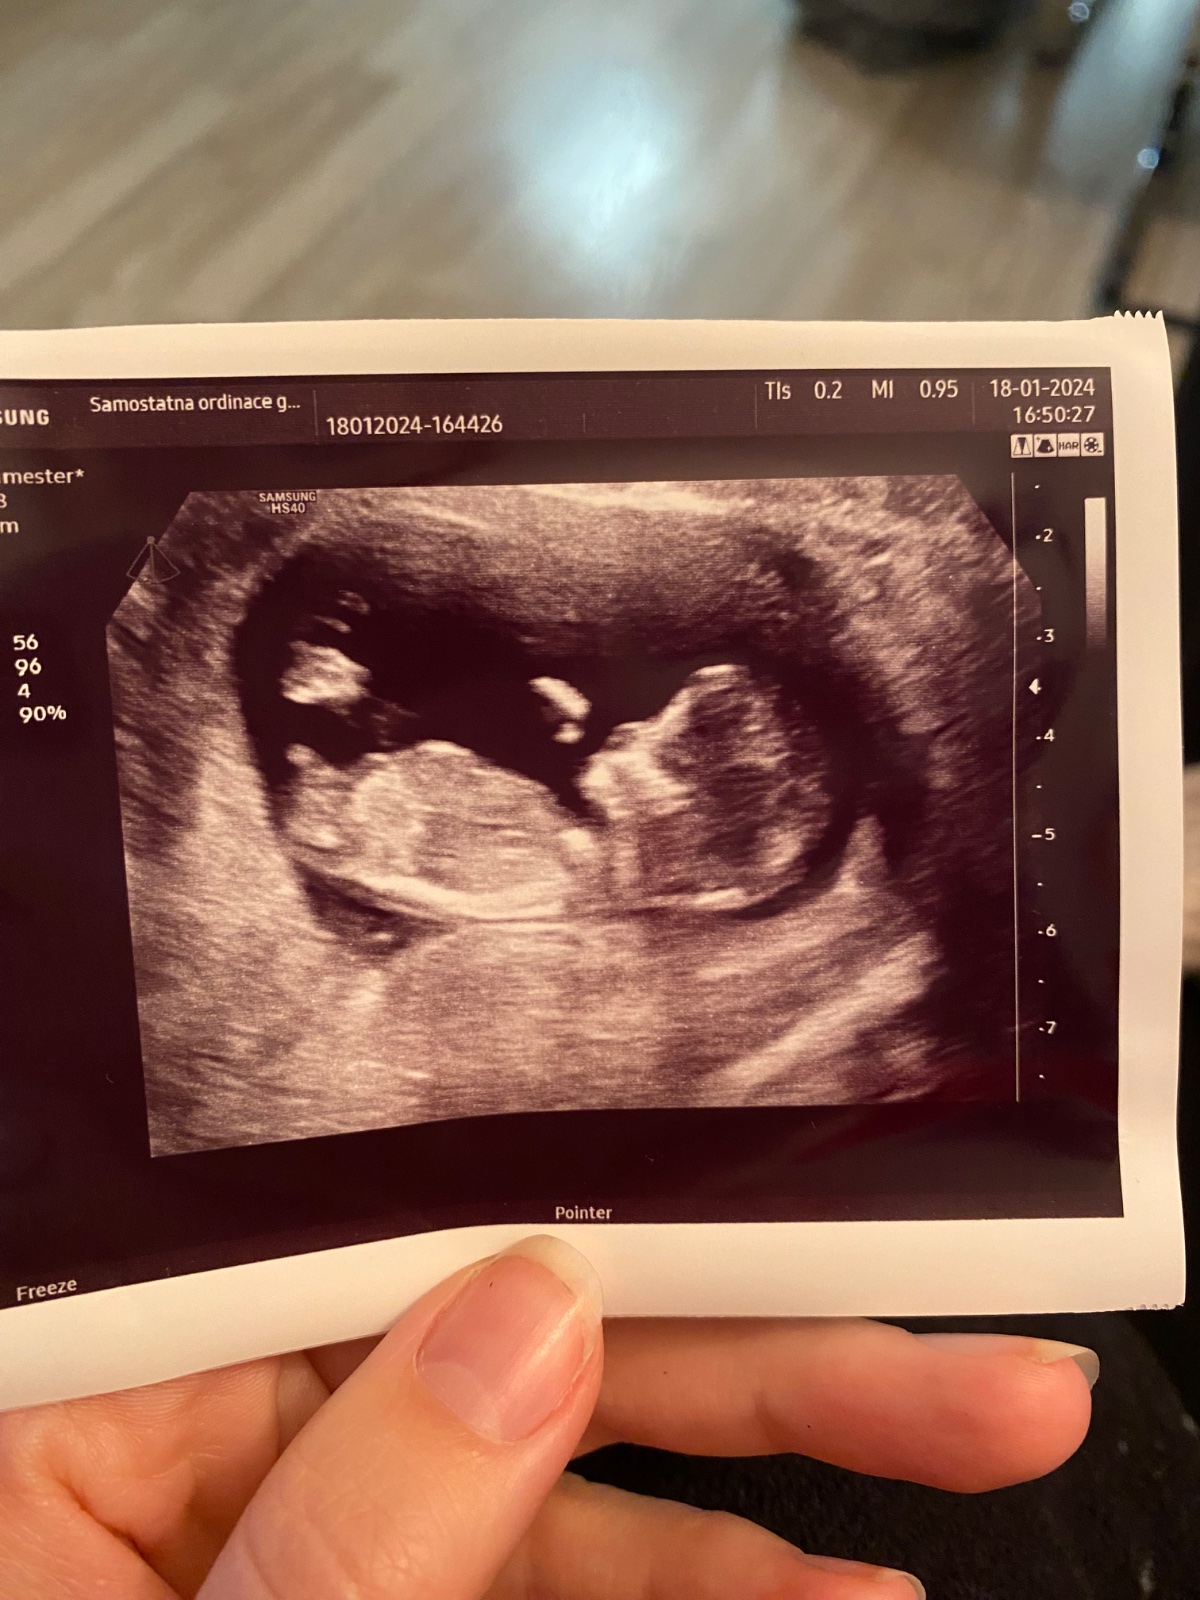

Ahoj holky a jak to vidíte tady,prosím? 🙂